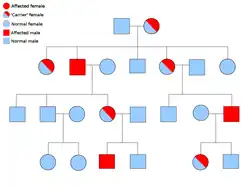

Two copies of every gene are present in all cells of the body and each one is called an allele. Most cancer syndromes are transmitted in a mendelian autosomal dominant manner. In these cases, only one faulty allele has to be present for an individual to have a predisposition to cancer. Individuals with one normal allele and one faulty allele are known as heterozygous. A heterozygous individual and a person with two normal alleles (homozygous) will have a 50% chance of producing an affected child.[9] The mutation in the inherited gene is known as a germline mutation and a further mutation in the normal allele results in the development of cancer. This is known as Knudson's two-hit hypothesis, where the first hit of the gene is the inherited mutation and the second hit occurs later in life.[2] As only one allele needs to be mutated (as compared to both in so-called "sporadic cancers"), the individual has a higher chance of developing the cancer than the general population.[10]

Less often, syndromes may be transmitted as an autosomal recessive trait. Both alleles of a gene must be mutated in autosomal recessive disorders for an individual to have a predisposition to cancer. A person with two recessive alleles is known as homozygous recessive. Both parents must have at least one faulty allele in order for a child to be homozygous recessive. If both parents have one mutant allele and one normal allele (heterozygous) then they have a 25% chance of producing a homozygous recessive child (has predisposition), 50% chance of producing a heterozygous child (carrier of the faulty gene) and 25% chance of produced a child with two normal alleles.[9]